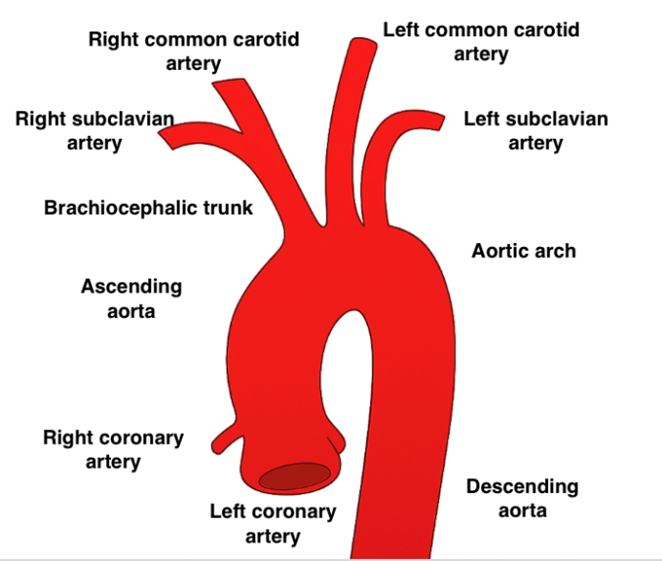

The internal carotid artery is a key component of the anterior cerebral circulation. Its embryonic development is linked to the third pair of aortic arches, around the fourth week of gestation [1]. Agenesis, defined as the complete absence of formation of the ICA and its bony canal, is a very rare anomaly (incidence < 0.01%), often asymptomatic but potentially responsible for neurological events.

The ICA normally forms from the third pair of aortic arches and the aortic sac between the third and fifth weeks of gestation. Early interruption of this development results in agenesis, defined by the total absence of the artery and its bony canal in the base of the skull [3]. On the other hand, late regression would result in hypoplasia or aplasia (very thin or threadlike artery, but with preserved bony canal). These distinctions have important diagnostic and prognostic implications.

Figure 1: 3rd Aortic Arch.